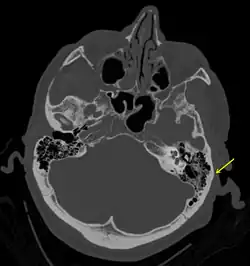

| A subtle temporal bone fracture as seen on a CT scan | |

Temporal bone fractures

Acute injury to the internal carotid artery (carotid dissection, occlusion, pseudoaneurysm formation) may be asymptomatic or result in life-threatening bleeding. They are almost exclusively observed when the carotid canal is fractured, although only a minority of carotid canal fractures result in vascular injury. Involvement of the petrous segment of the carotid canal is associated with a relatively high incidence of carotid injury.[10]